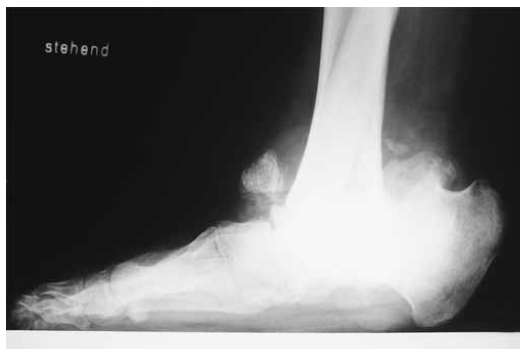

The patient is a 13-year-old girl with complete insensitivity to pain. She is the product of the first pregnancy of a non-consanguineous Austrian couple. At birth her weight, length and head circumference were around the 75th percentile. Family history was unremarkable. The prenatal and postnatal history of the child was normal. At the age of 9-years she went skiing for which she developed ankle joint fracture without pain. Primarily, it was not diagnosed as a pathological fracture. She underwent a series of vigorous investigations. Complete blood count, erythrocyte sedimentation rate, blood electrolytes, calcium, phosphate, alkaline phosphatase and blood sugar were normal. Liver, kidney, and thyroid function tests were normal. Clinical examination showed a normal-looking girl with no specific dysmorphic features. Neurological examination showed no response to pain, but normal responses to touch and temperature as well as normal tendon reflexes. Muscle power was normal. The results of electromyographic and nerve-conduction studies were normal. Abdominal and renal ultrasounds were normal. On the bases of skeletal survey, a Charcot ankle joint was identified. Anteroposterior ankle radiograph with 3/4 foot showed Charcot changes more marked over the left joint with multiple loose bodies. Amortise view of the ankle showed accumulated trauma associated with progressive lytic changes was the reason to develop severe Charcot joint. Dislocation, fragmentations and avascular necrosis were evident (fig. 1). lateral view of the ankle showed accumulated trauma associated with progressive lytic changes was the reason to develop severe Charcot joint. Dislocation, fragmentations and avascular necrosis were evident (fig. 2) Lateral ankle joint radiograph showed advanced stage of Charcot joint with disastrous destruction of the ankle joint associated with extensive callus formation and complete distortion of the joint shape (fig. 3). At this stage, we discussed the treatment options with the parents and the girl. Amputation was an option, which was totally rejected by the family. Then, we decided to perform surgical correction. All the pathologic tissue of the ankle joint was resected and the distal tibia and the calcaneus were fixed together by using Ilizarov frame. Tibial-calcaneal fusion turned out to be successful and 6 months later we were able to remove the external fixator. The girl became able to walk with the aid of special shoes.

Fig. 2. Lateral view of the ankle showed accumulated trauma associated with progressive lytic changes was the reason to develop severe Charcot joint. Dislocation, fragmentations and avascular necrosis were evident

Fig. 3. Lateral ankle joint radiograph showed advanced stage of Charcot joint with disastrous destruction of the ankle joint associated with extensive callus formation and complete distortion of the joint shape. Accumulated trauma associated with progressive lytic changes was the reason to develop severe Charcot joint. Dislocation, fragmentations and avascular necrosis were evident